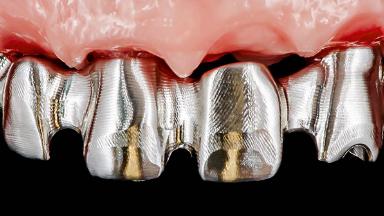

Rehabilitating an Edentulous Maxilla with a Fixed Dental Prosthesis Following Provisional Immediate Loading

This case features the flapless computer-guided placement of 7 bone-level implants, distributed to provide maximal support for the prosthetic framework. A rigid one-piece metallic framework was utilized as an interim restoration to reduce the risk of fracture associated with this prosthetic design. As part of the clinical examination, the SAC Assessment Tool was used, resulting in a surgical and restorative risk classification as “complex”.

Defining Characteristics Fully edentulous upper jaw to be rehabilitated with an implant-borne fixed dental prosthesis

Loading Protocol Immediate